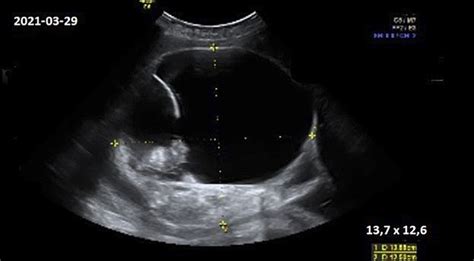

- Ultragarsinis tyrimas (echoskopija): Tai vienas svarbiausių tyrimų, leidžiančių įvertinti vaisiaus vystymąsi, jo dydį, širdies veiklą ir nustatyti, ar jis atitinka nėštumo savaitę. Taip pat galima diagnozuoti negimdinį nėštumą ar kitas problemas.